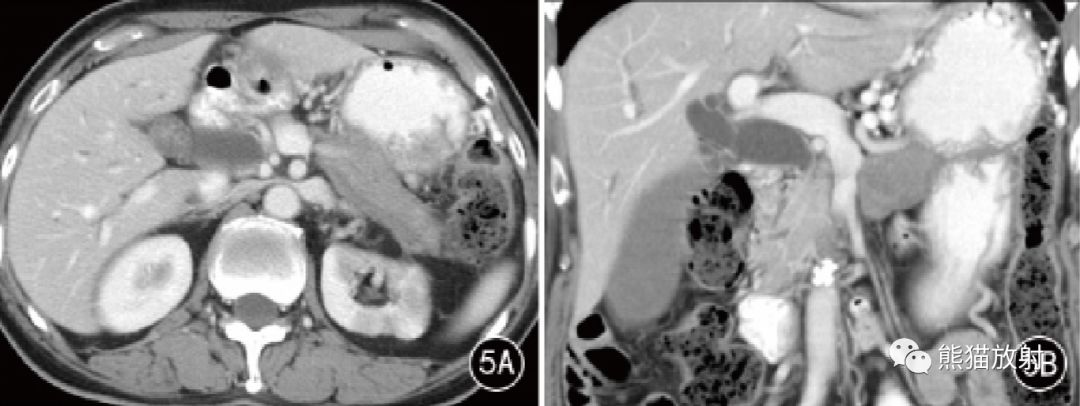

图5 男,81岁。AIP 胰腺体尾部弥漫性病变, CT门静脉期胰腺体尾部弥漫性肿胀,周围见包壳,胰管未见扩张;左肾实质多发低强化区。门静脉期冠状位MPR示胰腺段胆管狭窄,管壁增厚,继发肝内外胆管扩张。